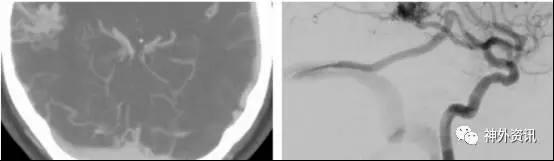

图4. 简单的颞叶外侧面AVMs。这是位于颞叶下方颞下回的病变,P2段分支颞后动脉于病灶后缘进入并参与供血。注意向后方引流的粗大引流静脉(见侧位和正位的颈内动脉造影)。主要的供血来源于颞叶上动脉。对于优势半球颞叶后方的病变,需要注意保留Wernicke语言区,它位于距颞极约5厘米的颞中、颞上回。